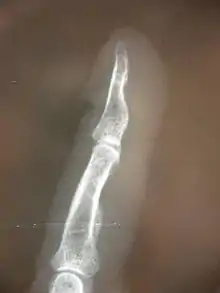

La luxation articulaire est définie comme un déplacement évident entre deux os. La subluxation est un processus plus discret de déplacement entre deux articulations, pas nécessairement décelé sur une radiographie ou une imagerie à résonance magnétique.

Subluxations des membres périphériques

Celles-ci suivent également la règle précitée de subluxation articulaire avec des conséquences neurologiques dans certains cas. Néanmoins, les conséquences de déplacements osseux sur les parties périphériques du corps sont souvent beaucoup plus prévisibles en termes de conséquences sur les fonctions nerveuses, tant au niveau moteur qu'au niveau sensoriel, ou encore pour ce qui est des fonctions végétatives (épidermiques et circulatoires notamment)

Pour les membres supérieurs et inférieurs

De même, lorsqu'une structure comme l'articulation ulno-radial (coude) se retrouve partiellement déplacée ou réduite en mobilité, le nerf radial peut subir une compression induite par le radius lui-même ou induite par l'hypertonicité des muscles environnants, réduisant ainsi ses fonctions sensorielles ou motrices. Une manipulation spécifique sur le radius aura l'effet de décomprimer le nerf incriminé, les effets sensoriels ou moteurs seront alors modifiés, soit instantanément soit sur une période allant jusqu'à 76 heures.